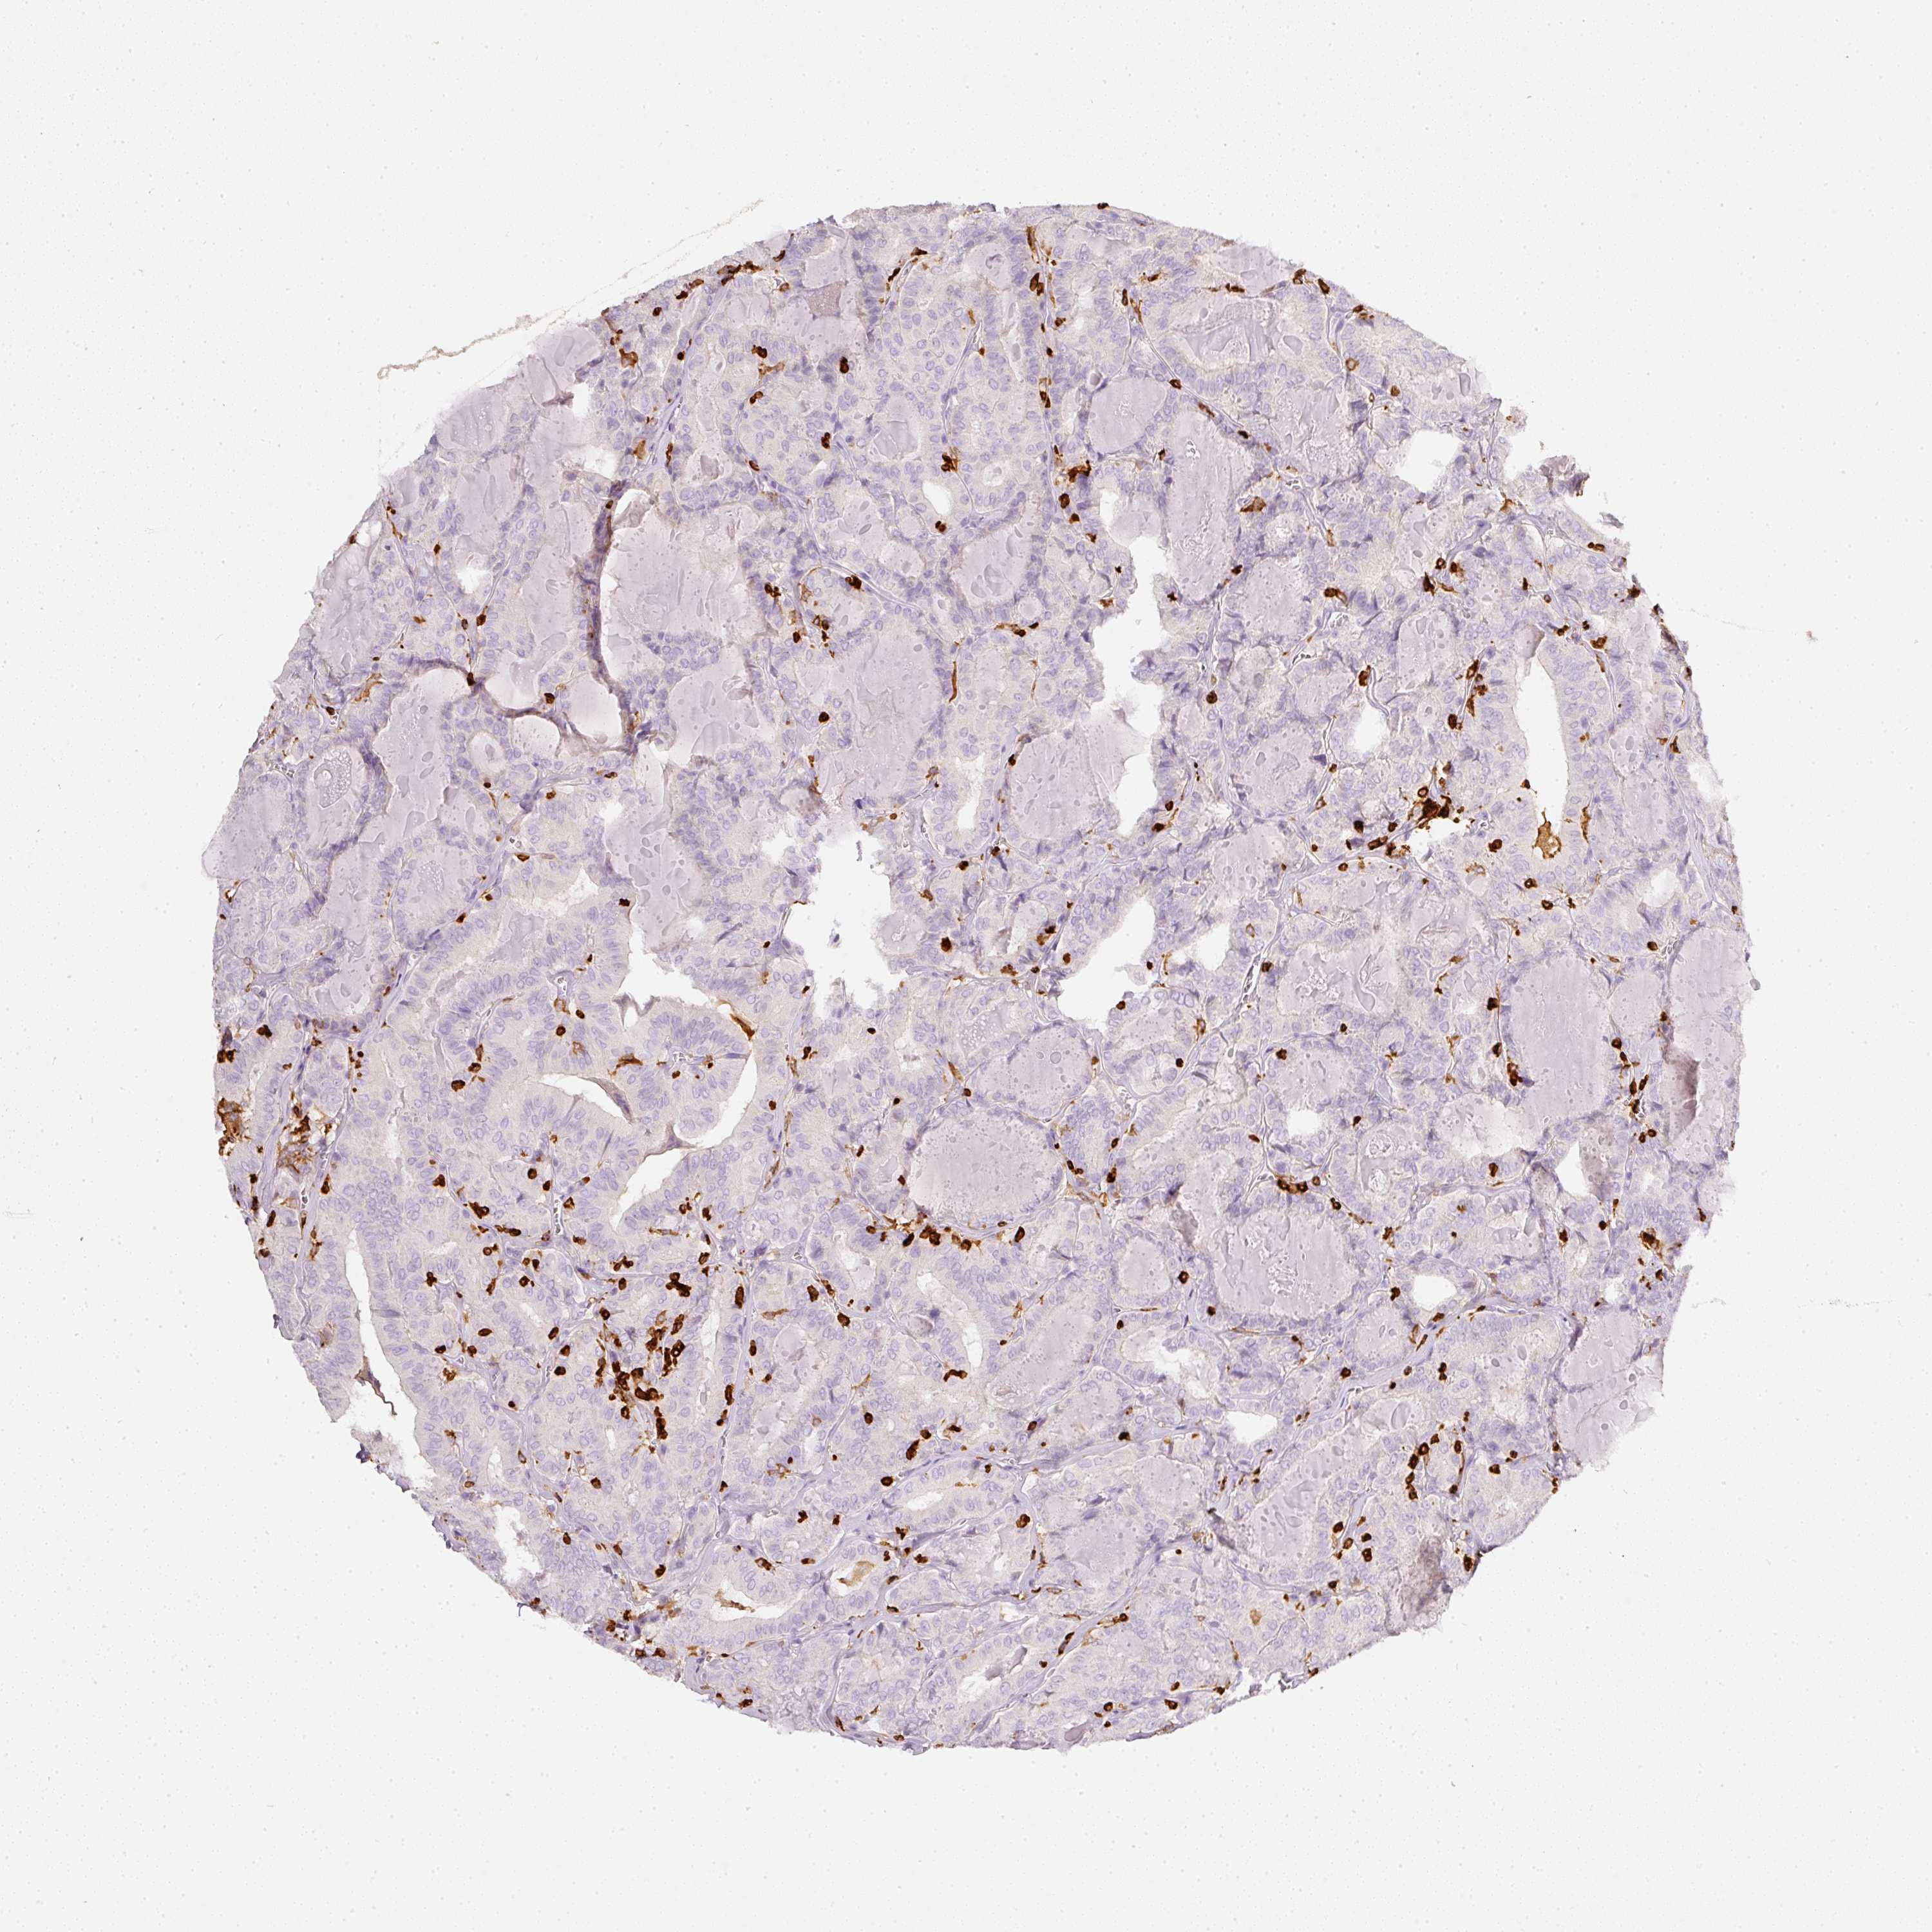

THYROID CANCER - Protein expressioni

A mouse-over function shows sample information and annotation data. Click on an image to view it in a full screen mode. Samples can be filtered based on level of antibody staining by selecting one or several of the following categories: high, medium, low and not detected. The assay and annotation is described here.

Note that samples used for immunohistochemistry by the Human Protein Atlas do not correspond to samples in the TCGA dataset.

Antibody stainingi

Antibody staining in the annotated cell types in the current human tissue is reported as not detected, low, medium, or high, based on conventional immunohistochemistry profiling in selected tissues. This score is based on the combination of the staining intensity and fraction of stained cells.

Each image is clickable and will lead to virtual microscopy that enables deeper exploration of all samples and also displays staining intensity scores, fraction scores and subcellular localization as well as patient and tissue information for each sample.

Antibody HPA018849

Antibody HPA019536

Antibody CAB033987

Staining

High

Medium

Low

Not detected

Intensity

Strong

Moderate

Weak

Negative

Quantity

>75%

75%-25%

<25%

None

Location

Nuclear

Cytoplasmic/membranous

Cytoplasmic/membranous,nuclear

Papillary adenocarcinoma, NOS

Follicular adenoma carcinoma, NOS